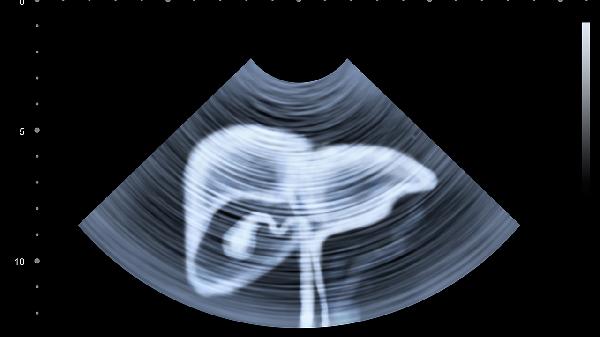

小兒腹部淋巴結(jié)腫大可通過熱敷、調(diào)整飲食、藥物治療、物理治療、手術(shù)治療等方式治療。小兒腹部淋巴結(jié)腫大通常由感染、免疫反應(yīng)、腫瘤、炎癥、外傷等原因引起。